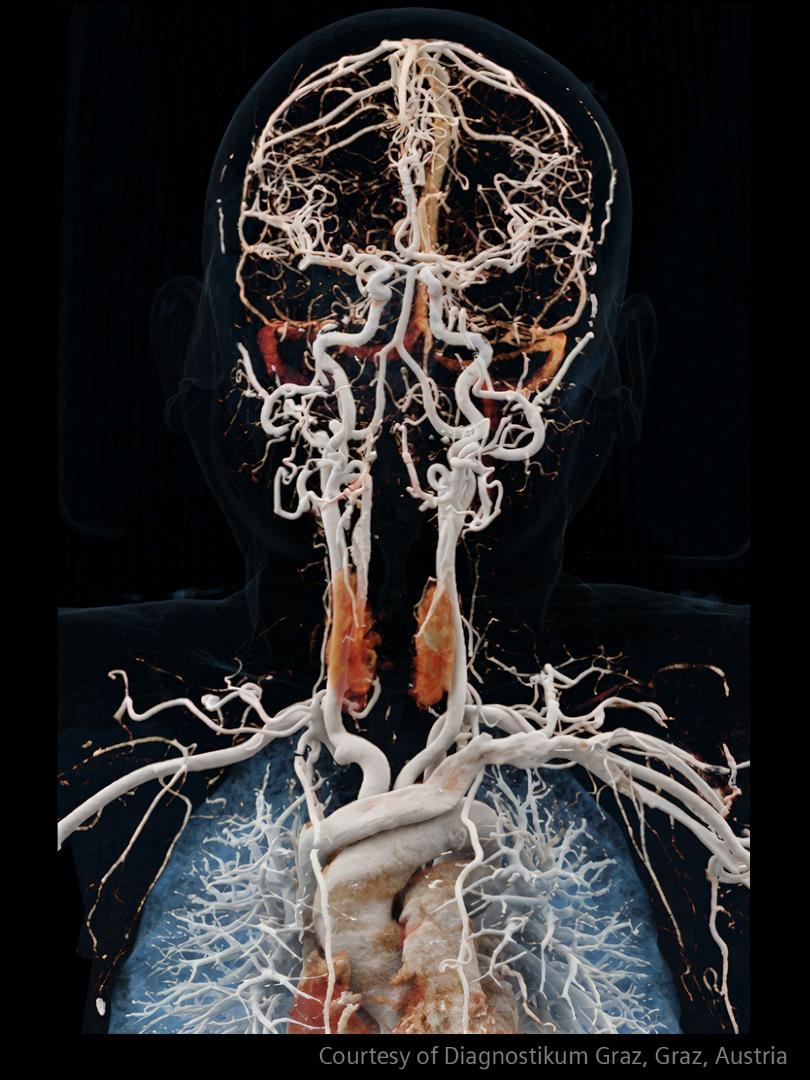

How advanced imaging and AI transform stroke workflow

In stroke care, time is brain. Rapid and accurate imaging is crucial to assess the extent of brain injury and guide immediate treatment. Angiography, MRI, CT, ultrasound, and lab diagnostics are essential tools in identifying stroke type, location, and severity. Advances in imaging technology now allow for even faster acquisition, improved resolution, and enhanced visualization of brain tissue and blood vessels. Innovations such as perfusion imaging, real-time vascular mapping, and AI-assisted diagnostics are transforming stroke workflows and enabling precise, timely interventions.